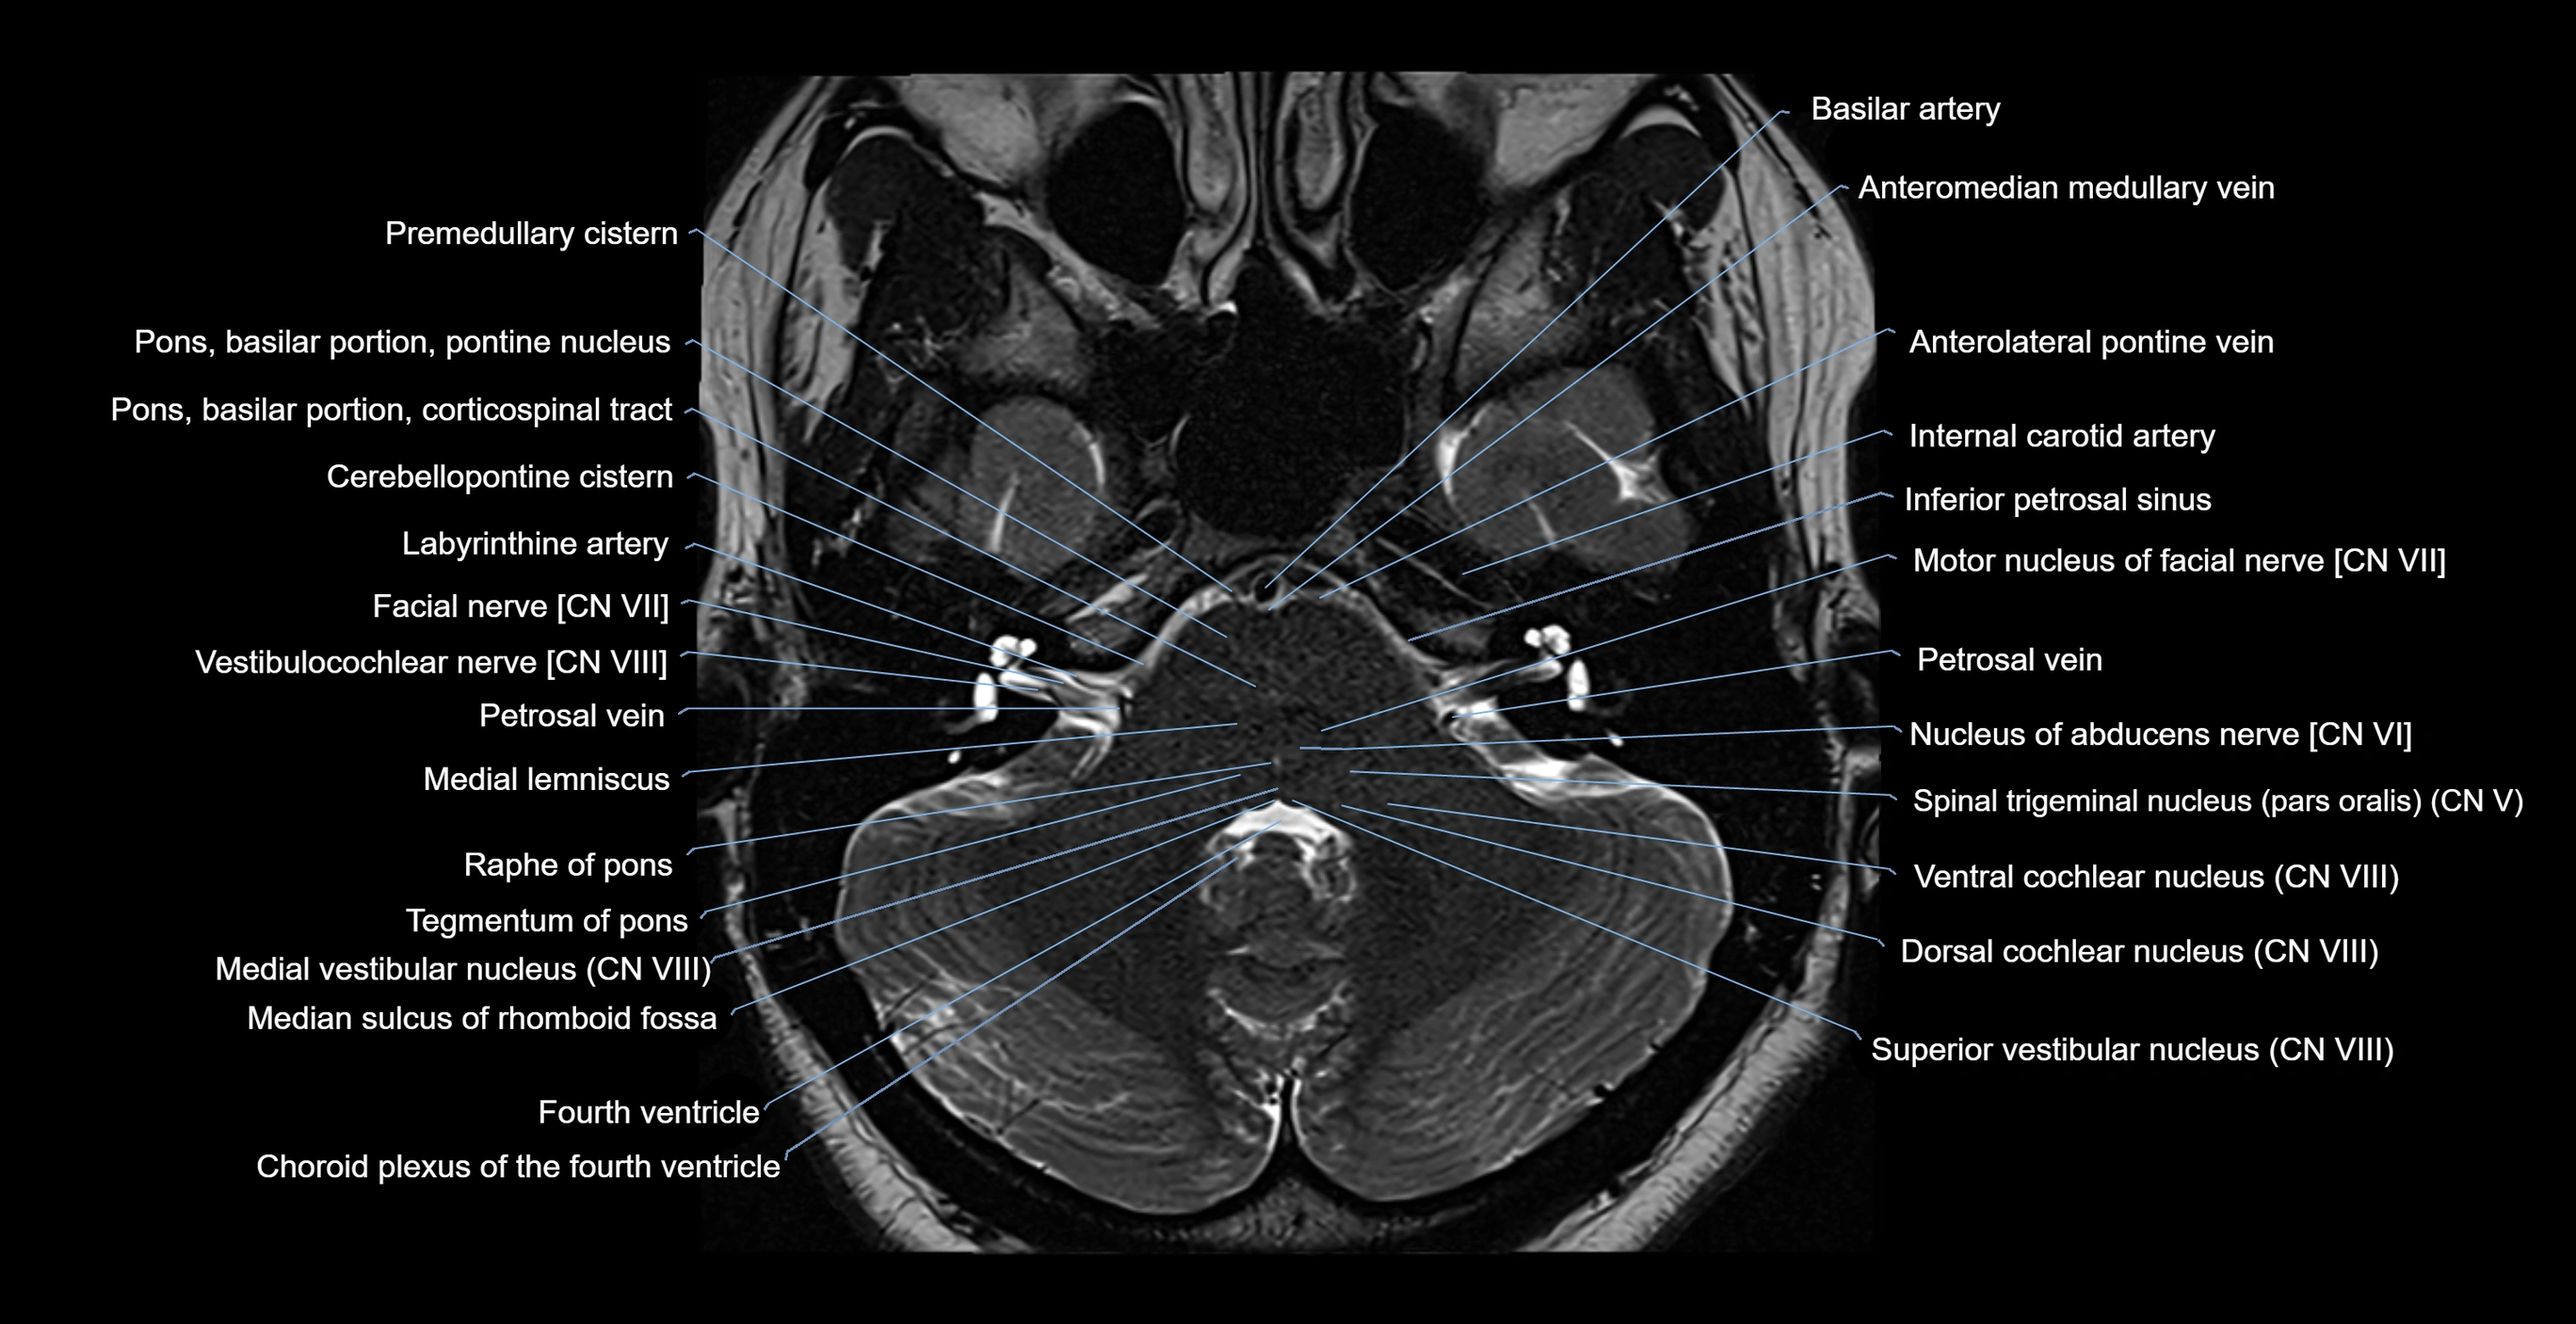

MRI images